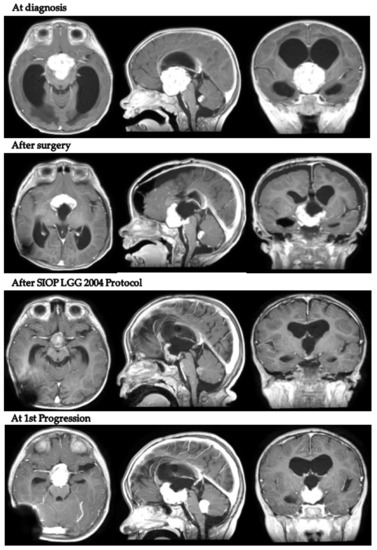

Intriguingly, in patient 9, despite tumor progression requiring a second surgical debulking after LGG 2004 standard induction treatment, the body weight continued to increase (+2.1 kg in 9 months). Figure 2 presents MRI scans of patient 9 at varying tumor stages.

Figure 2.

Axial, coronal and sagittal post-contrast T1-weighted MRIs of patient 9 at diagnosis, after neurosurgical biopsy and after the LGG 2004 induction protocol (1st progression).

MRIs at the end of first-line chemotherapy documented partial response in three cases and stable disease in five. Only one child (patient 9) progressed during first-line treatment, at the end of induction chemotherapy as per the LGG SIOP 2004 protocol (week 24).